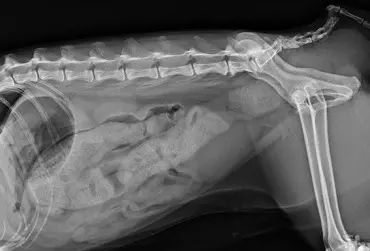

W artykule opisano przypadek dirofilariozy u psa wywołanej D. immitis. U badanego pacjenta stwierdzono patognomiczny obraz zmian w badaniu rentgenowskim i ultrasonograficznym układu sercowo-naczyniowego.